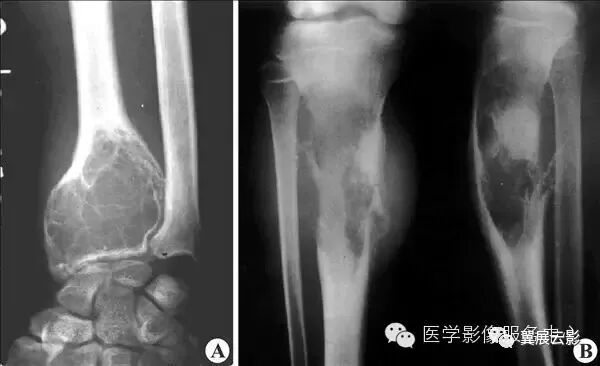

【普通放射图片】:

【影像表现】:X线正、侧位片(A、B)示右胫骨下端分叶状骨质破坏,周围骨质硬化(↑)。【影像诊断】:右胫骨下端慢性骨脓肿。